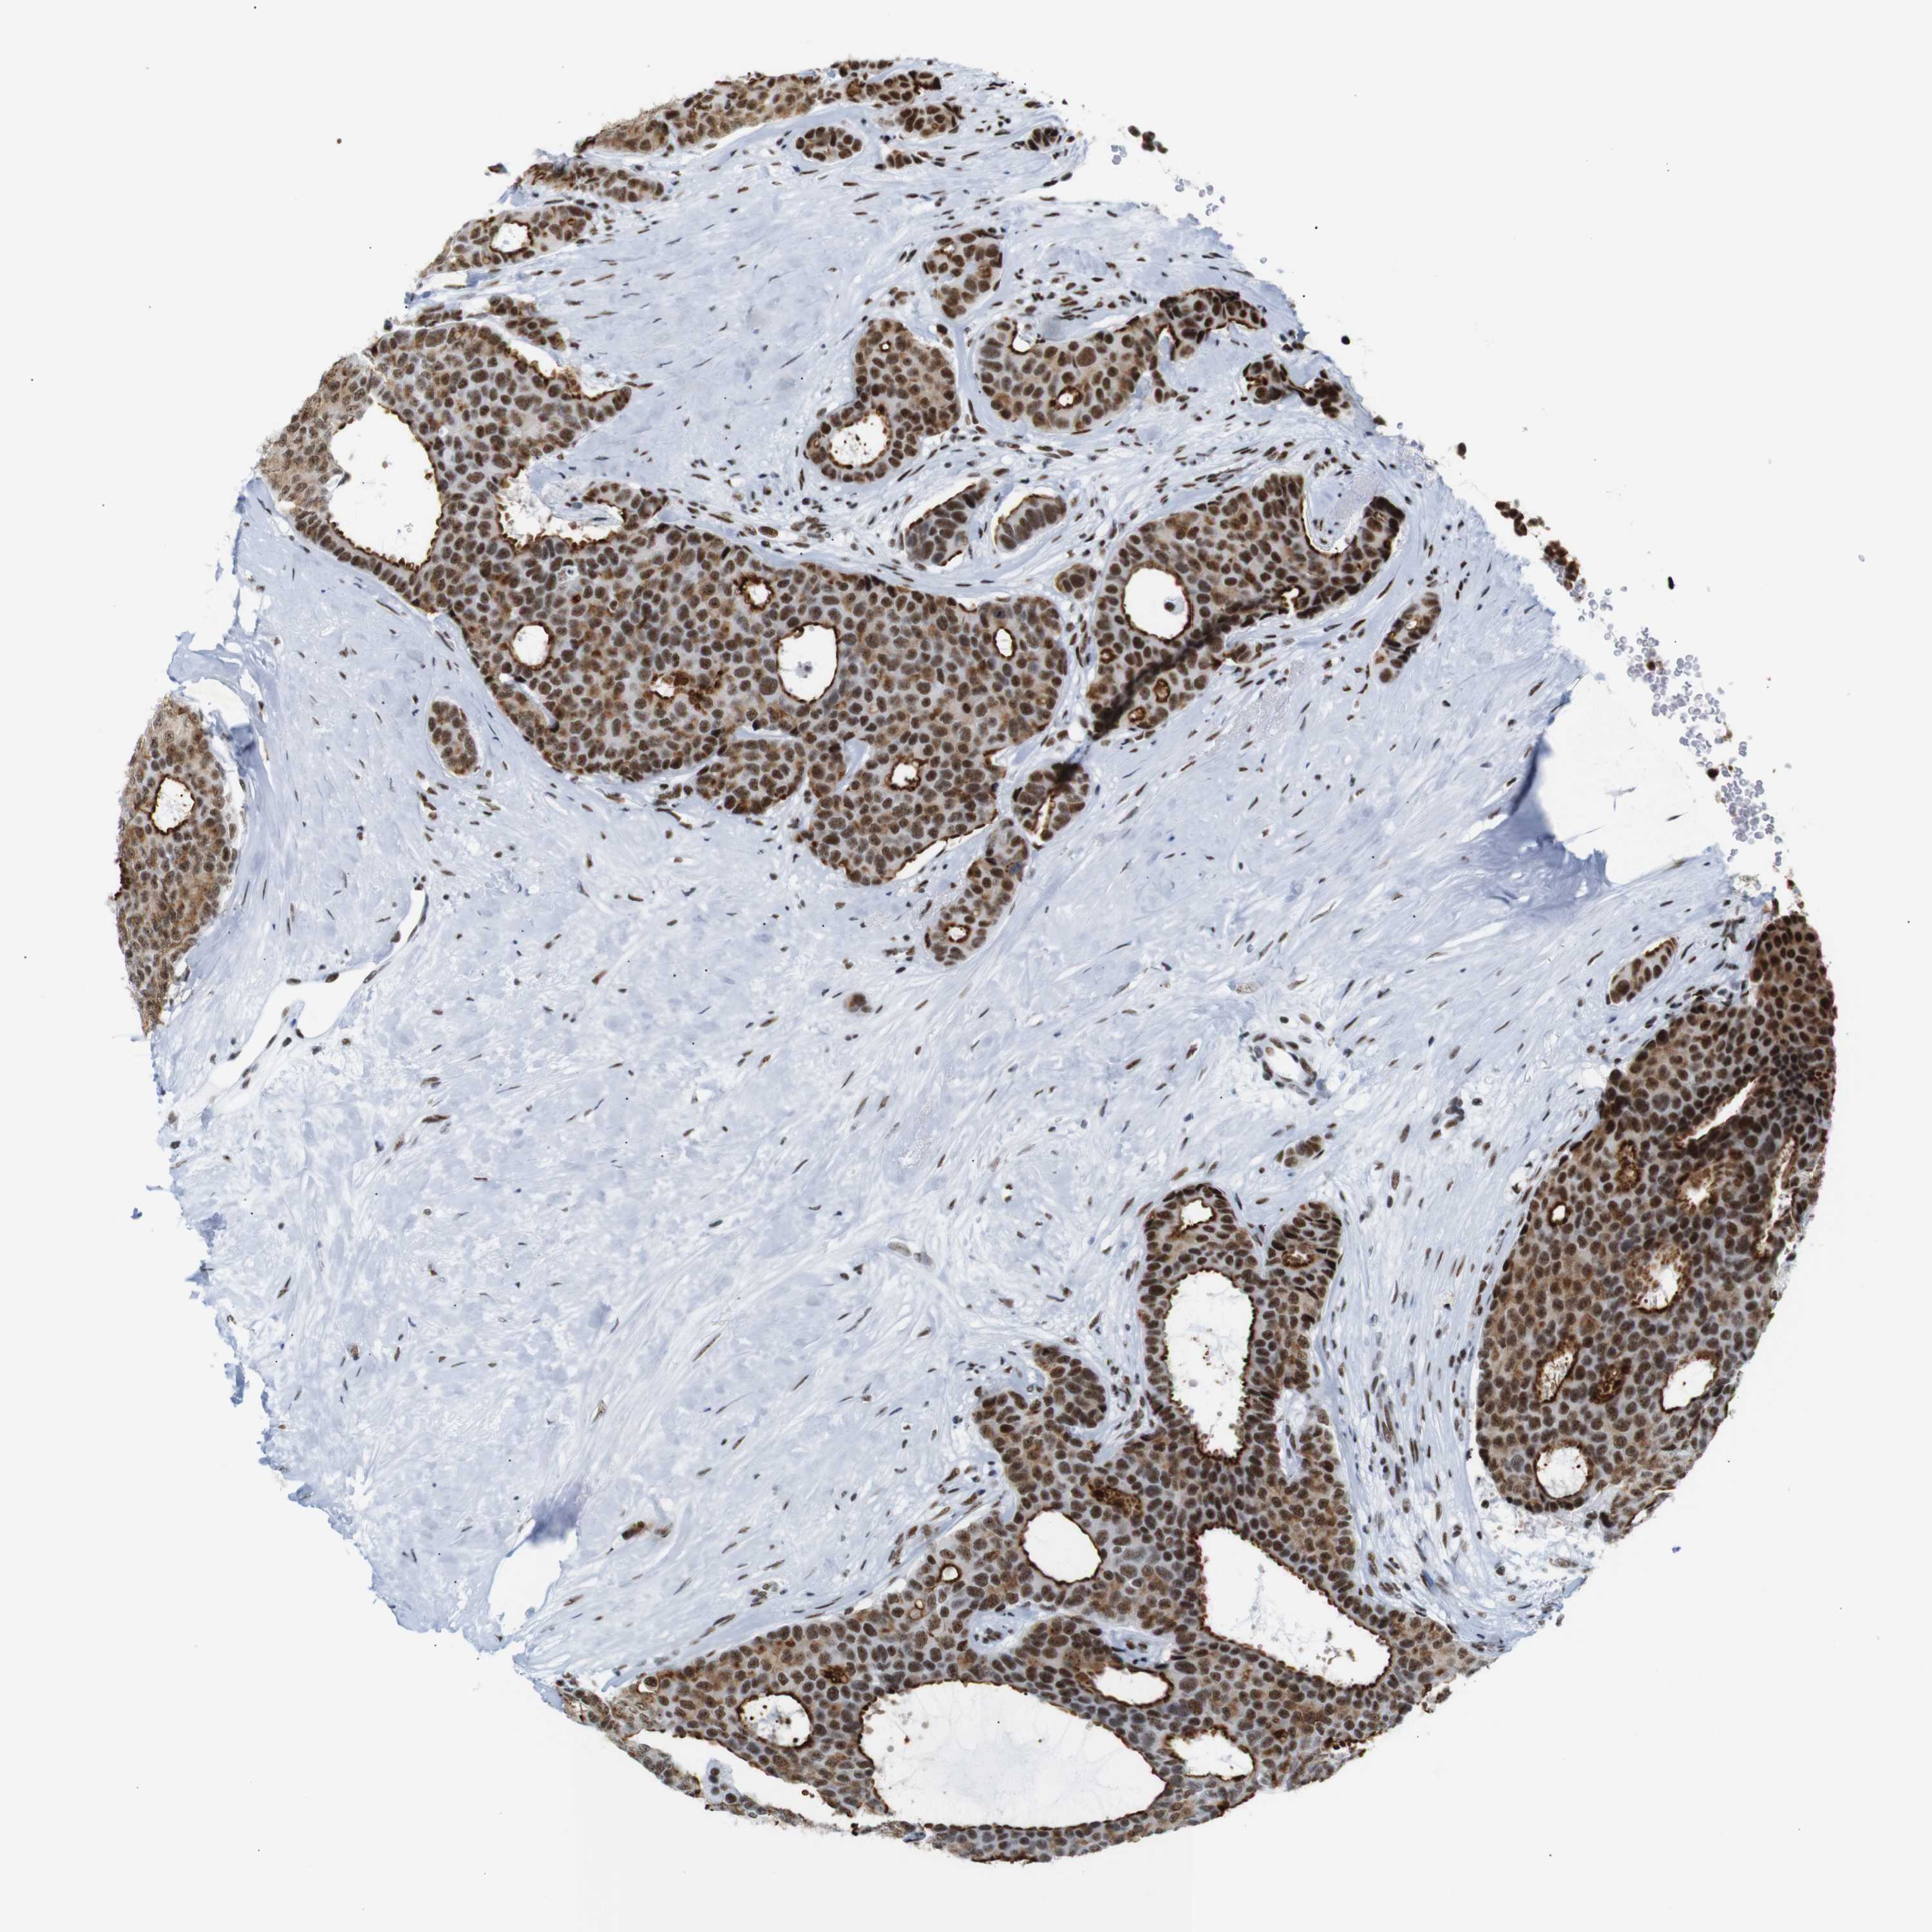

BRCA TCGA BRCA VALIDATION PROTEIN EXPRESSION